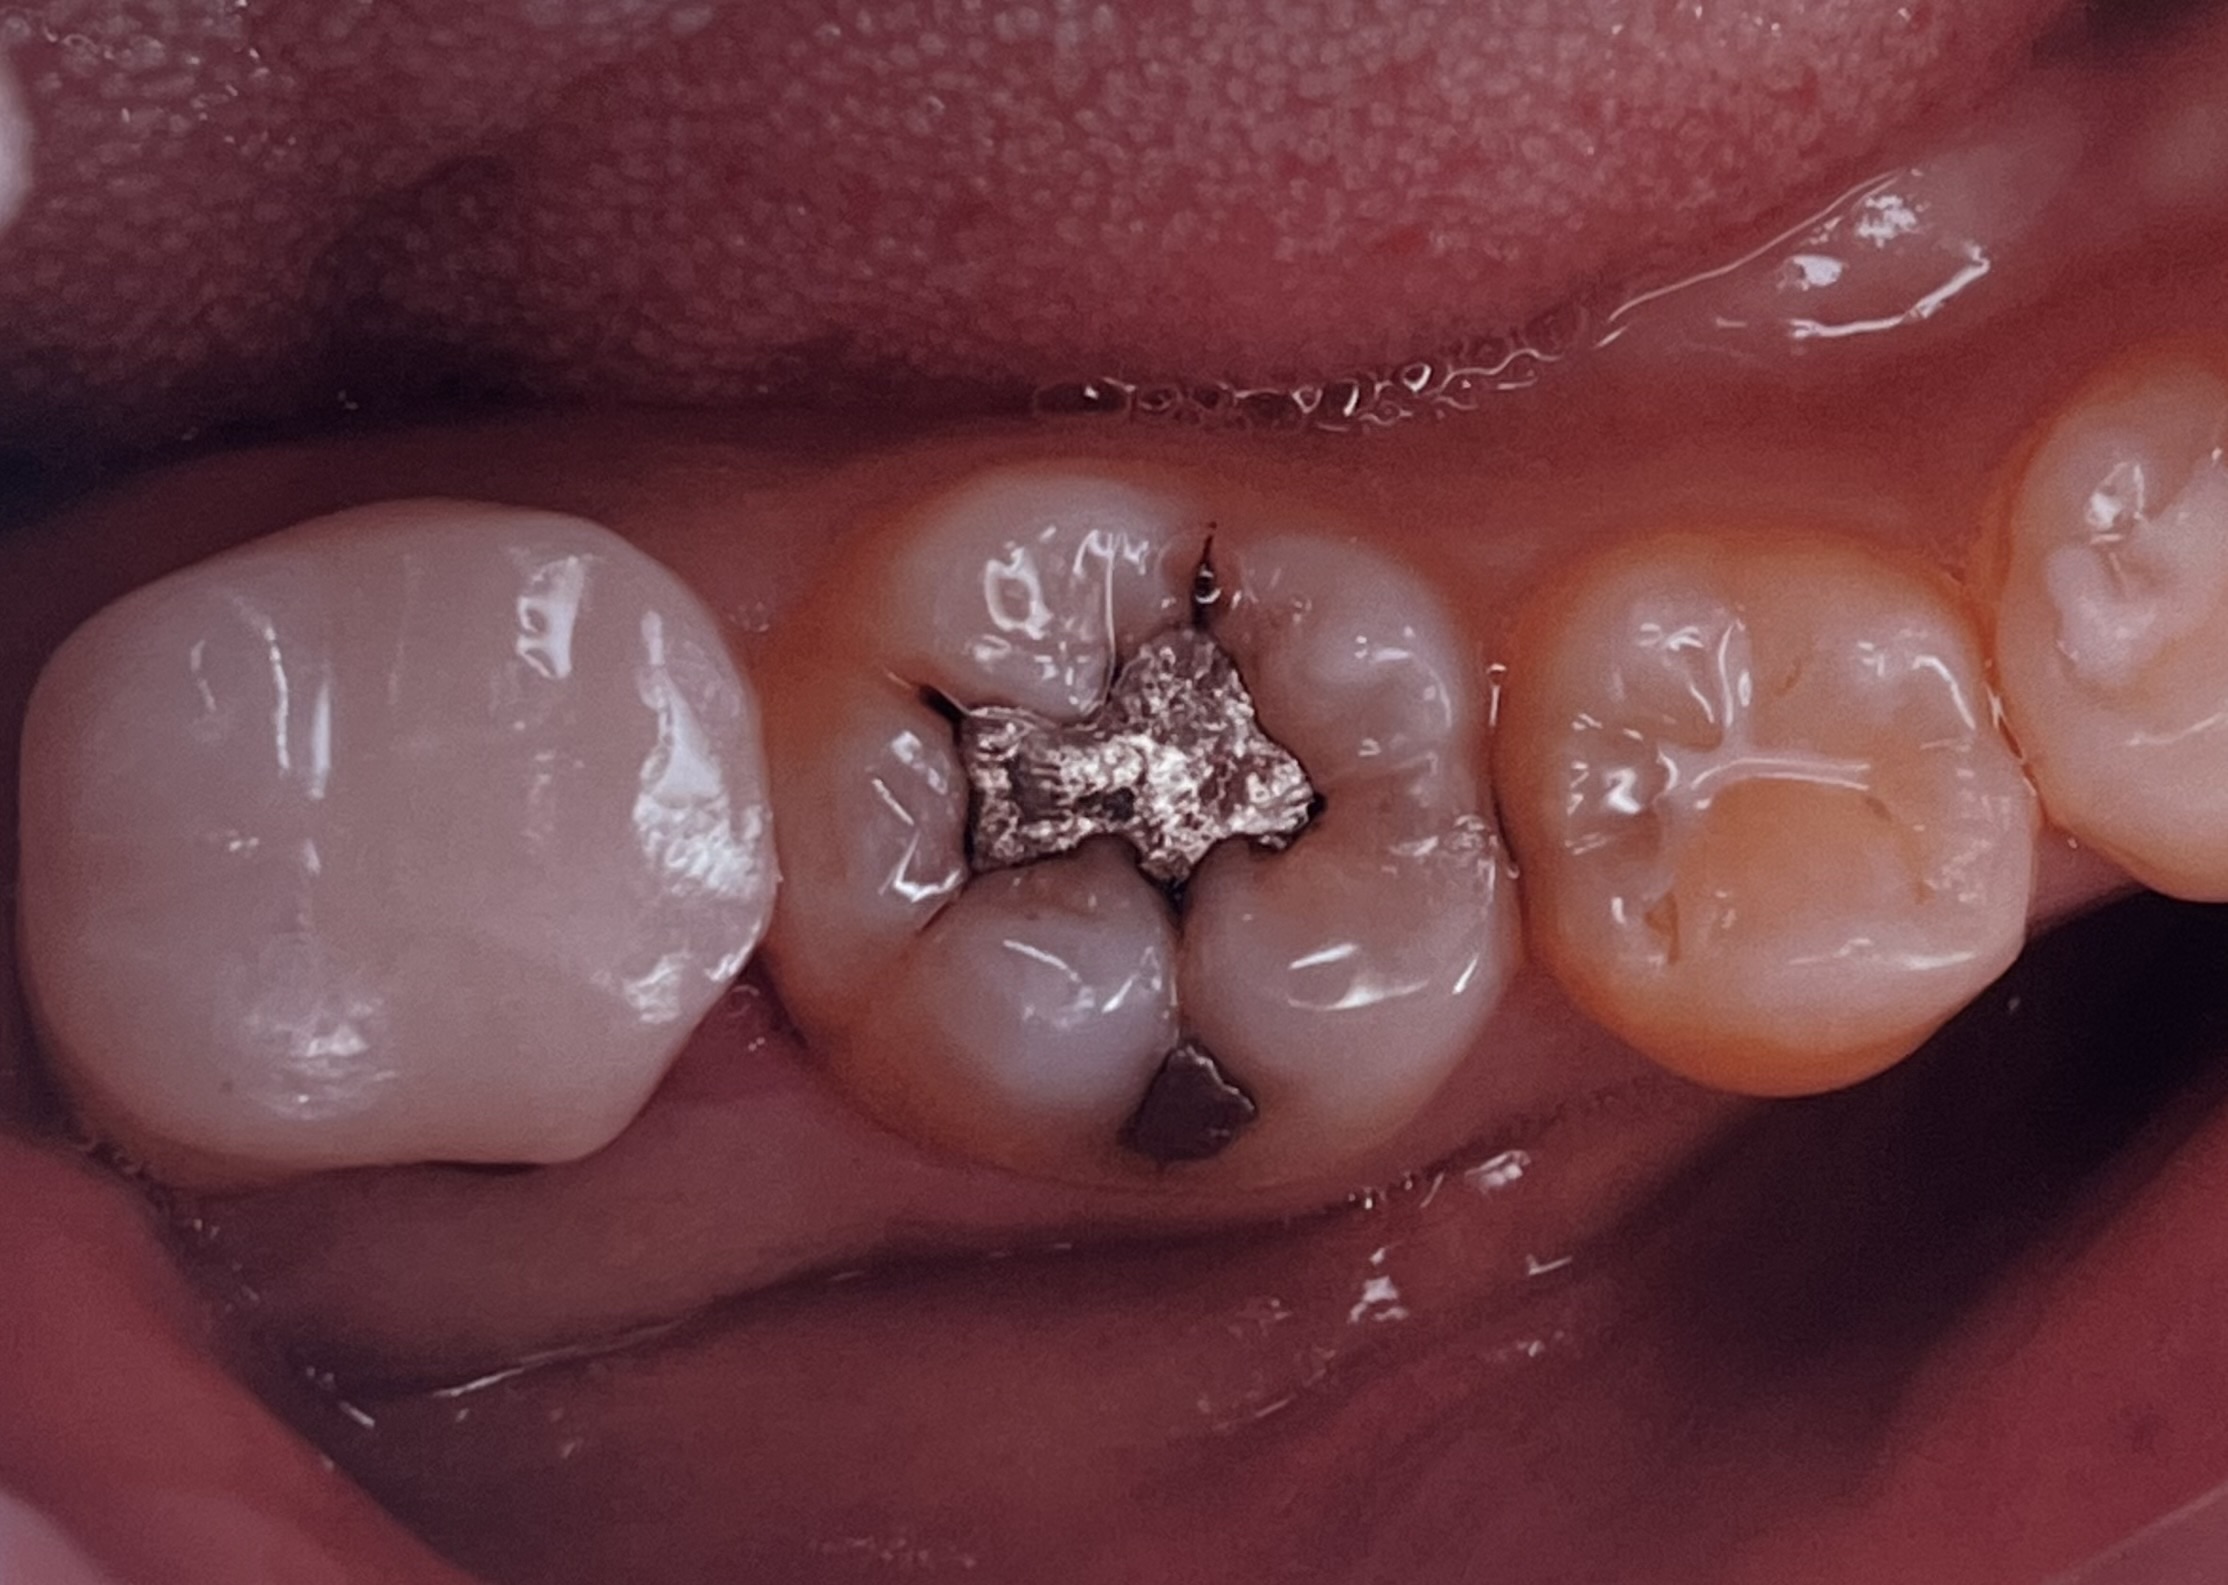

埼玉県志木市の佐藤デンタルクリニックです。今回は、部分的な銀歯を含む虫歯をぶぶんなセラミックで治療したものです。

しかし、銀歯治療には現代には即さない致命的な欠陥があります、特に今回あげた銀歯(アマルガム)と言われるおもにに昭和時代に行われた詰まる治療は、元々の治療が深いことが多く、神経まで到達してしまうことが多くほっておくと神経を取る治療になりやすい欠点があります、

また、アマルガムは物にもよりますが、水銀を含んでああることがあり、アレルギーの観点からも口の中に入れるのは良くないと現代では言われています、

当院での治療は、保険外にはなりますが、セレックという機械を用いて数時間で、麻酔からセラミックセットまでを行うものです、1dayトリートメントといいます、

今回の治療は、エナミックという弾力があり、かけにくい噛みやすいセラミックを用いて行なっています、価格は、65000-80000円(税別)となります、虫歯の大きさなどによっては全体を覆うものも良いかと思いますが、歯の歯質を残したい方にはこの治療がおすすめです、